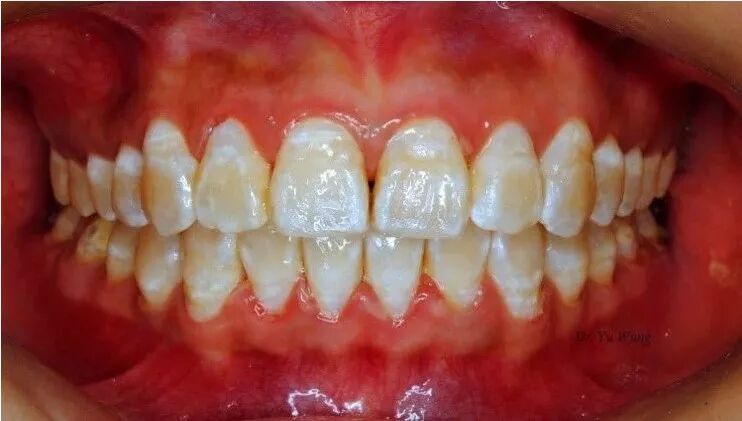

5.氟斑牙:氟化物摄入过量导致氟中毒(尤其会影响6岁以下的儿童),可能会使牙齿出现白色条纹或褐色斑点,即“氟斑牙”。

日常氟化物摄入主要来源于饮用水,年幼生活在饮水氟含量过高地区(>1.0ppm)容易导致氟斑牙,如煤矿地区、饮用地下水和井水等地区。但作为公共卫生措施,参考本区环境,在供水系统中添加非常少量的氟化物是有益的(WHO推荐最佳浓度为 0.7ppm),可以帮助控制蛀牙。

因饮水氟中毒导致的氟斑牙,呈花白外观